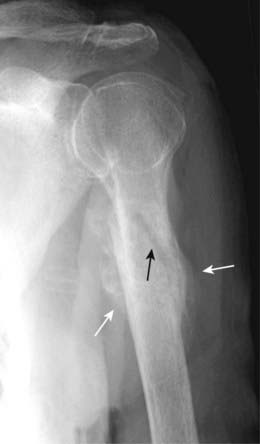

Figure 22-5 Dislocation and subluxation.

A, In a dislocation, the bones that originally formed the two components of a joint are no longer in apposition to each other (solid white arrows). The terminal phalanx is dislocated lateral compared to the middle phalanx. B, In a subluxation, the bones that originally formed the two components of a joint are in partial contact with each other. The humeral head (H) is subluxed inferiorly (solid white arrow) in the glenoid (G) because of large hematoma in the joint secondary to a fracture of the humeral neck (solid black arrow). The hematoma itself is not visible by conventional radiography.